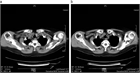

1. CTは、異物の描出のみならず、縦隔気腫、穿孔、腸閉塞など合併する重篤な病態の評価にも有用であり、可能であればCTの施行が望ましい(推奨度2)